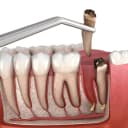

جراحی ریشه (آپیکوکتومی)

در مواردی که عفونت به ریشه دندان گسترش یابد و درمان ریشه کافی نباشد، جراحی ریشه دندان باقی مانده انجام می‌شود. در طی این جراحی، دندانپزشک بافت عفونی را از نوک ریشه دندان پاکسازی کرده و سپس انتهای ریشه را برش می‌زند. این نوع جراحی به دقت بالایی نیاز دارد و اغلب با استفاده از میکروسکوپ جراحی انجام می‌گیرد تا دقیق‌ترین حالت باشد.

جراحی دندان شکسته

اگر بخشی از دندان زیر لثه یا داخل استخوان فک شکسته باشد، جراحی دندان شکسته برای خارج کردن یا ترمیم آن لازم است. در این روش با برش لثه و گاهی تراش استخوان‌های اطراف، دندان را به صورت کامل یا قطعه قطعه خارج می‌کنند. جراحی دندان‌های شکسته به دقت بالایی نیاز دارد تا آسیبی به بافت‌های اطراف وارد نشود.